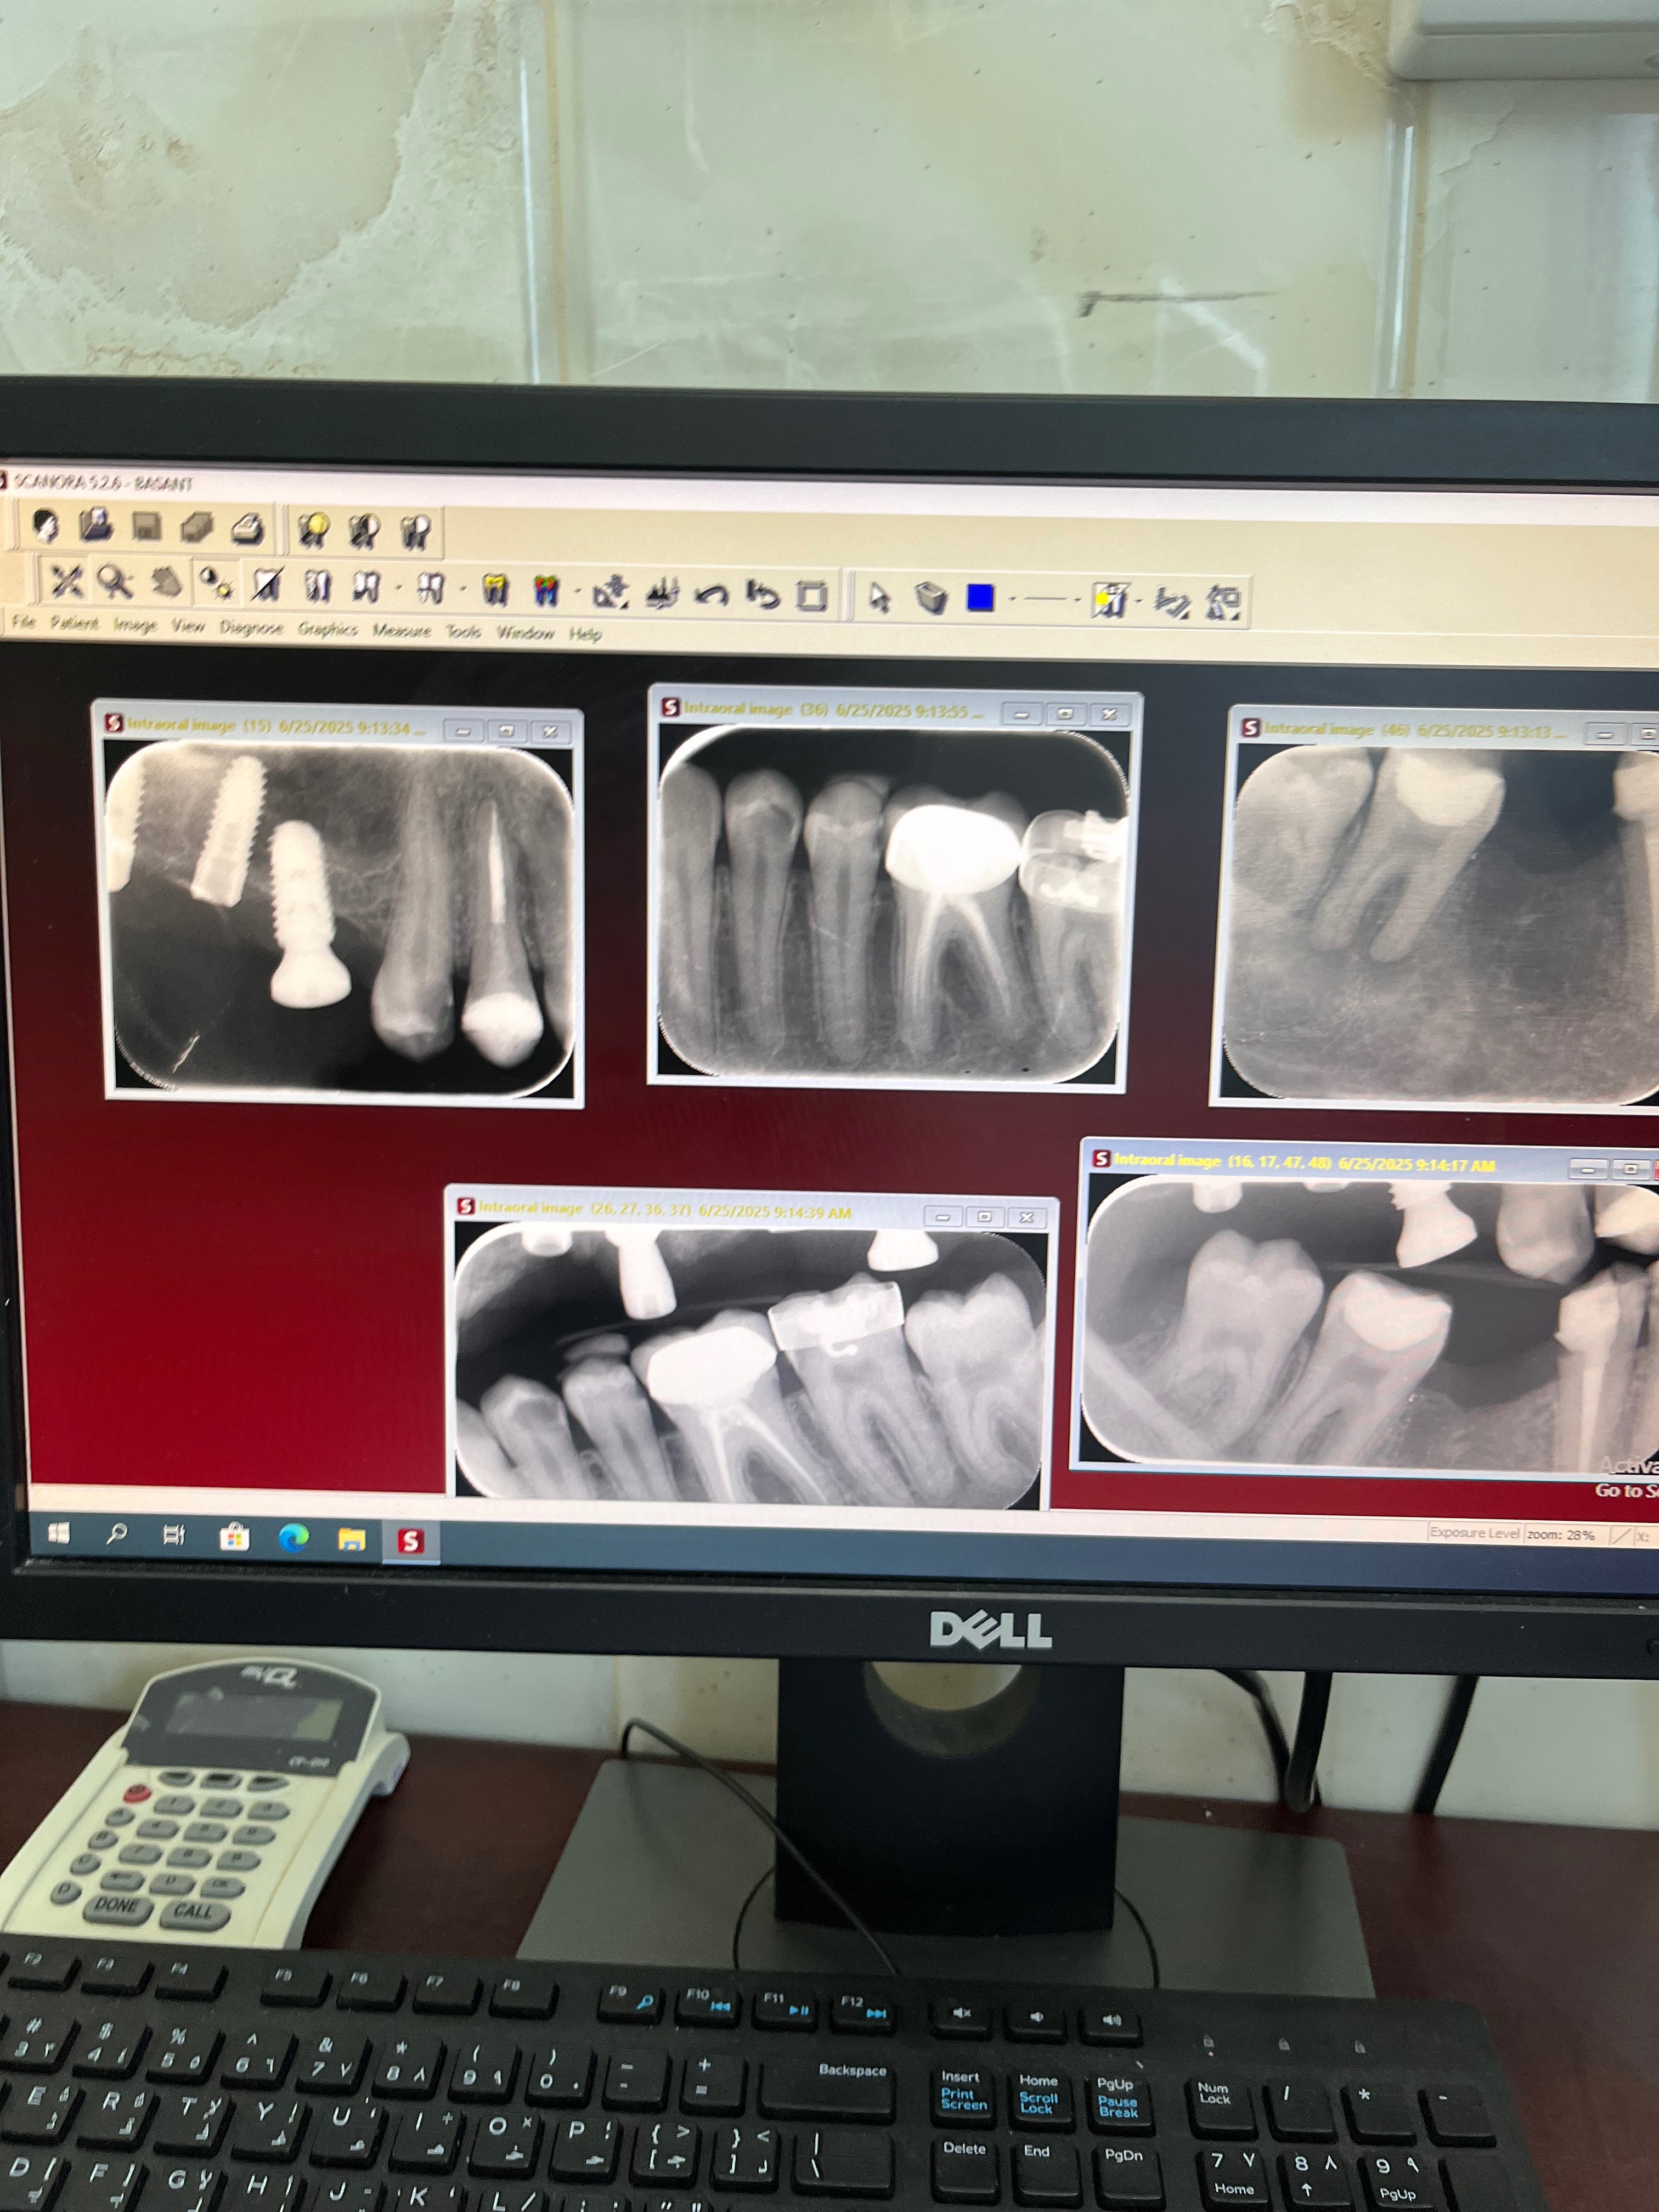

Several years ago, I went through a surgery in hopes of ending this struggle, but it ended in tragedy. The dentist performed the procedure carelessly, leaving both of my jaws misshaped and my implants misplaced. To make things worse, i couldn’t reach out to him and receive the missing parts of my implants to continue my treatment . After spending what I had on that failed procedure, I was left not only with greater health problems but also a heavy financial burden. For years I visited doctors, but many rejected my case due to its complexity.

Now, after a long search, I have finally found a specialist who can help me start over. But my case is no longer simple—the existing misplaced implants need to be removed, my jaws reconstructed, and bone grafting performed to replace the bone mass I have lost from years of delay. Several doctors will need to be involved in the surgery, making it far more complicated and costly than a normal double jaw surgery. This is my only chance to save my remaining teeth and prevent my condition from getting even worse.